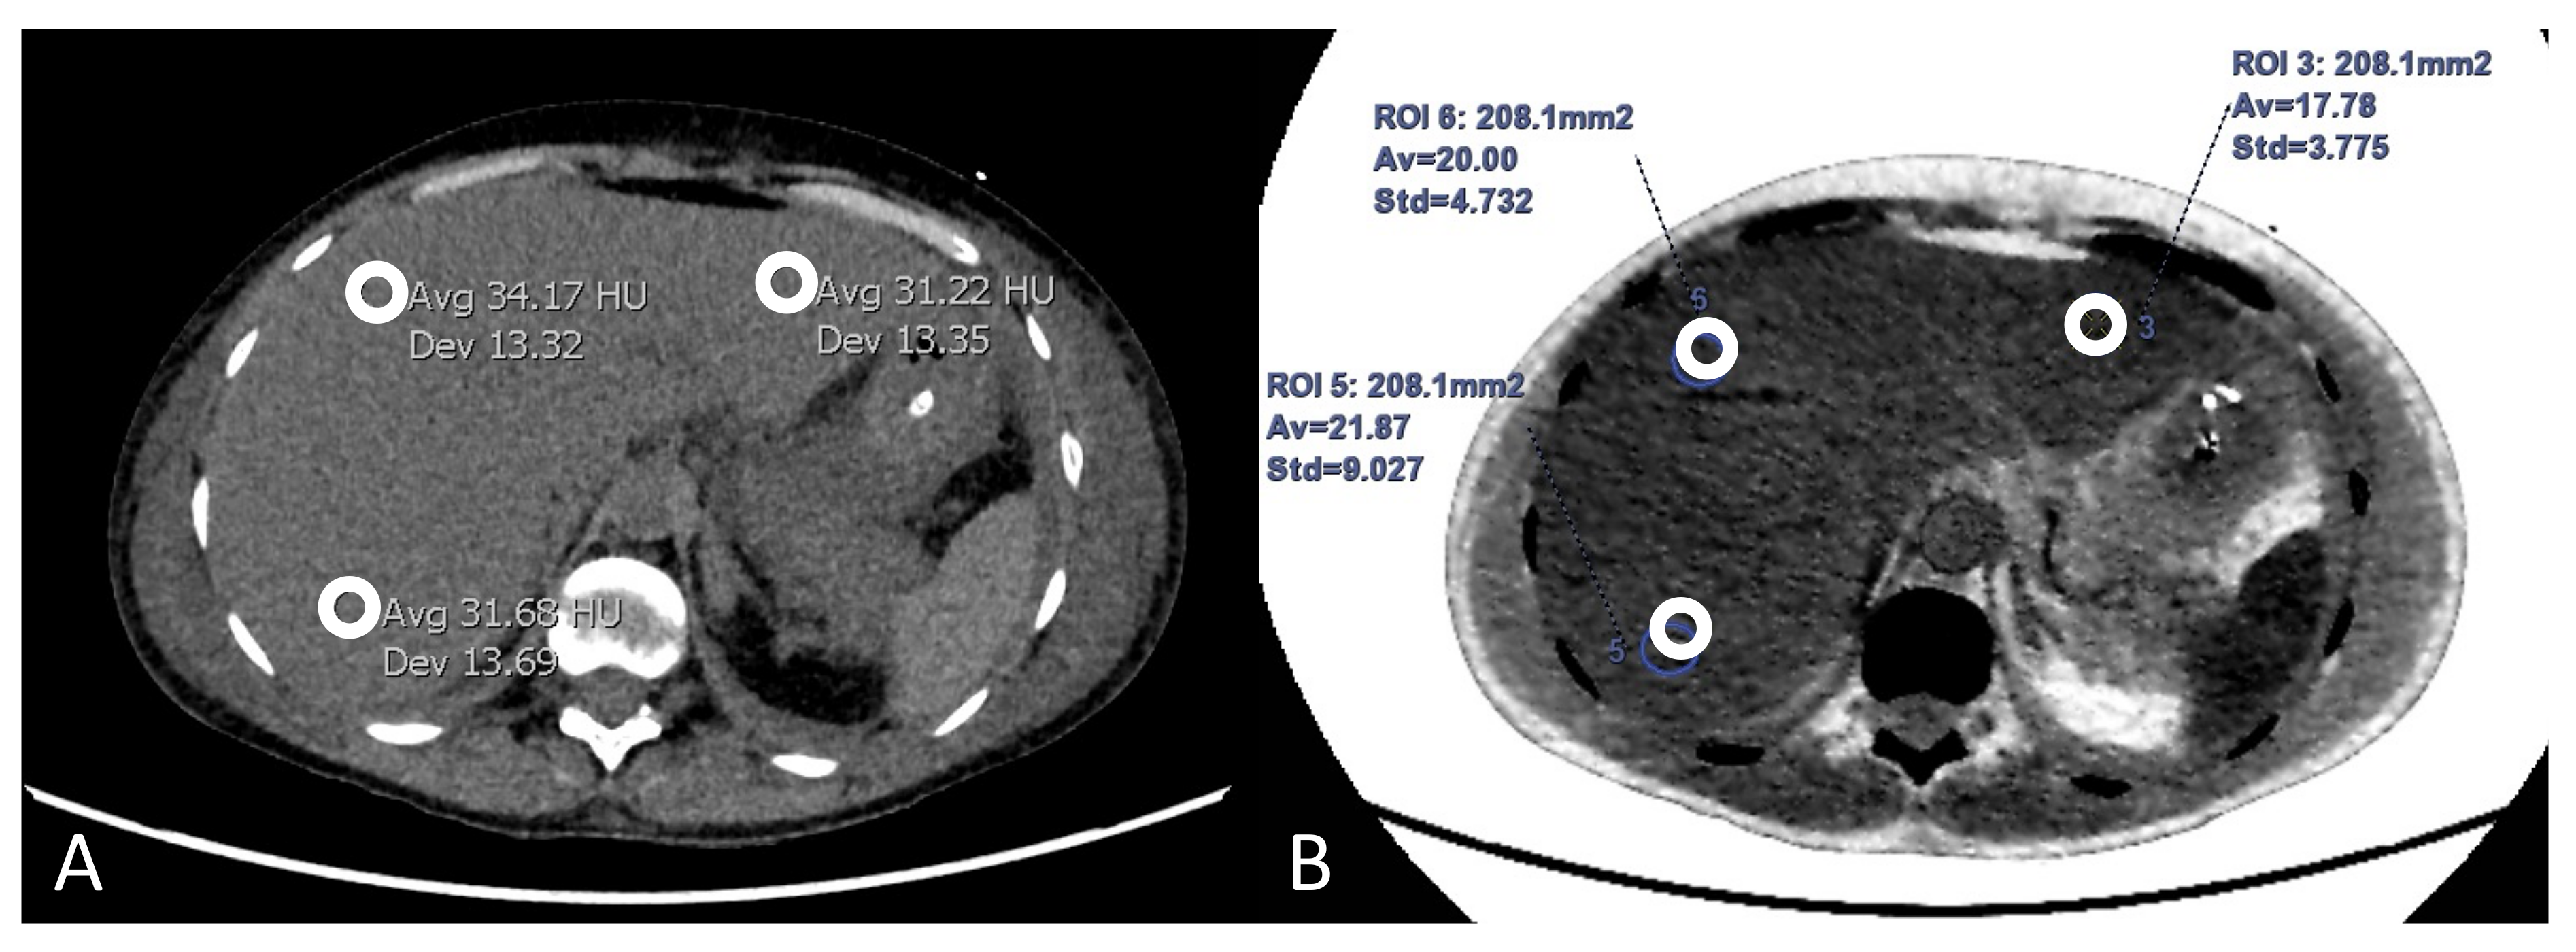

2.4. Image Analysis